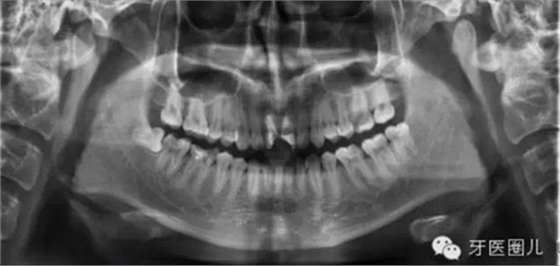

觀察術(shù)前X光片,設(shè)想達(dá)到一個(gè)理想的結(jié)果,然后用這一設(shè)想來(lái)指導(dǎo)每一治療步驟,這樣自然會(huì)提高我們的根管治療的操作水平。

患者外傷11 21簡(jiǎn)單冠折,選擇一次法完成冷牙膠充填3天后行樁修復(fù)。

一次法充填后最嚴(yán)重的疼痛發(fā)生在治療后24小時(shí)內(nèi),也有文獻(xiàn)說(shuō)是6-8個(gè)小時(shí),隨后患者反應(yīng)會(huì)大大減輕,與多次法比較治療的并發(fā)癥和成功率沒(méi)有差別,這個(gè)病例次日電話回訪患者患者無(wú)不適。